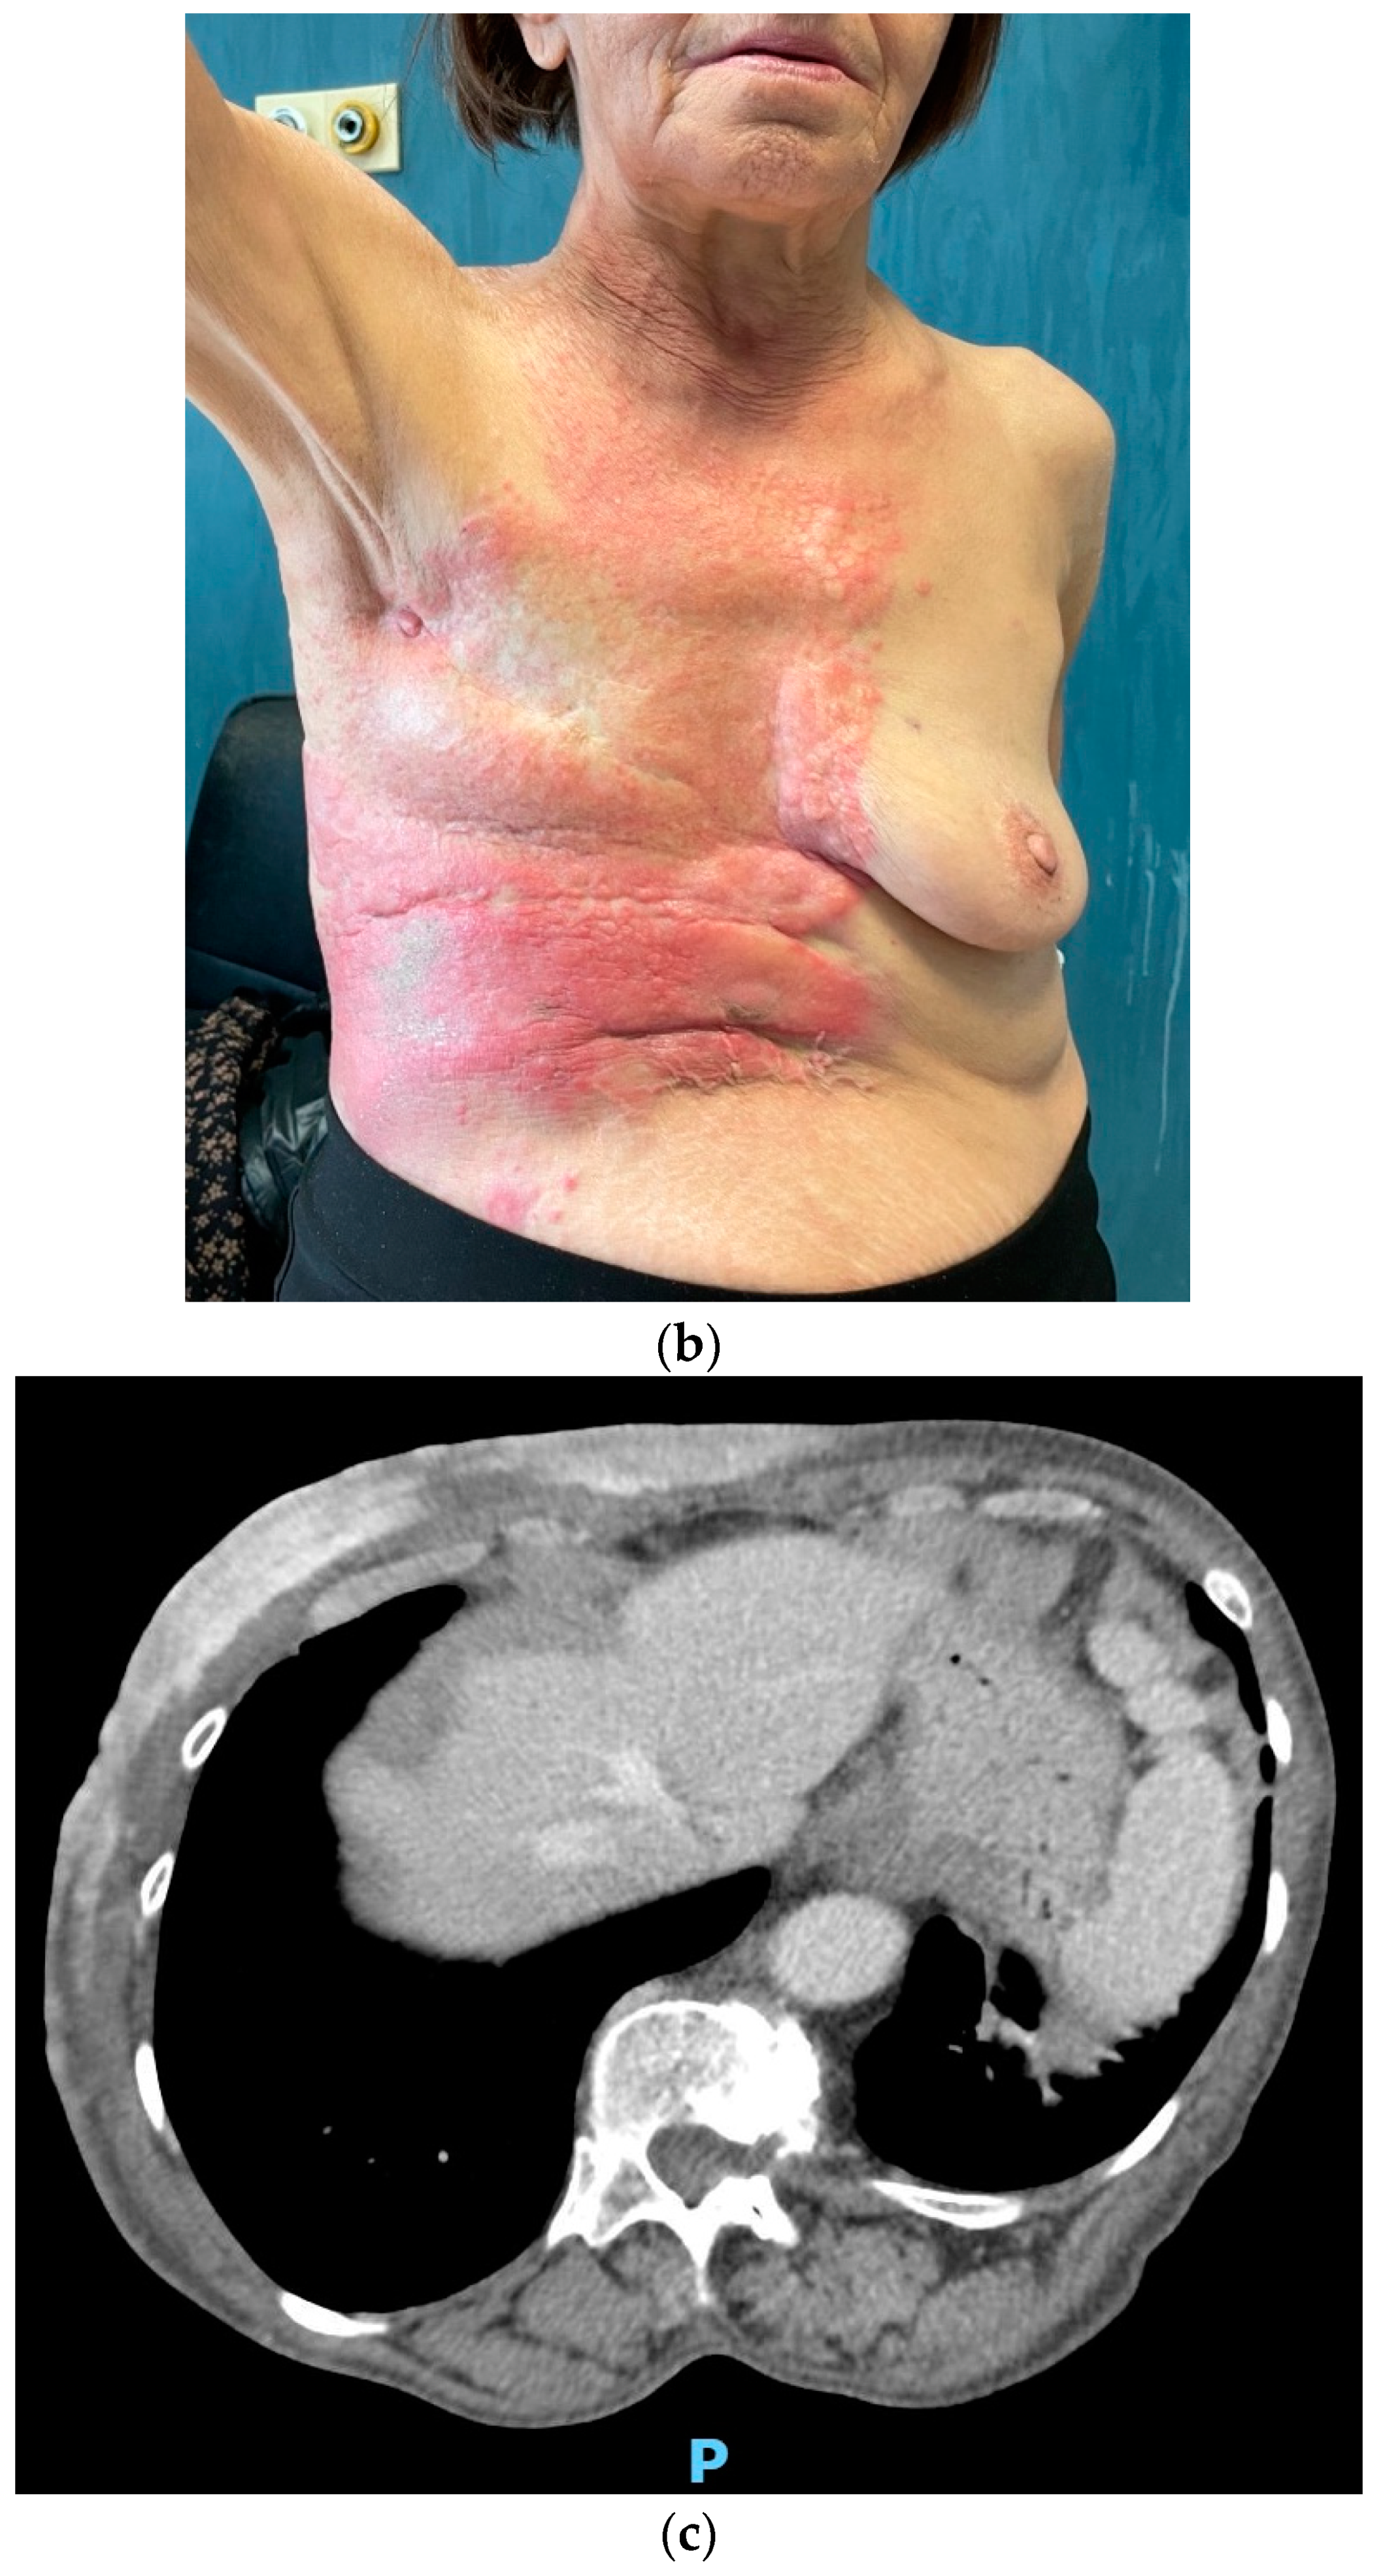

After experiencing initial disease stability with decreasing tumor markers (CEA 2.1 and CA15.3 22.3 IU/mL), in November 2021, unequivocal cutaneous progression occurred, with ulceration and spreading of the erythematous lesions to the upper abdomen (Figure 4). CEA remained below the upper limit of normal, while CA15.3 increased to 80 IU/mL.

Figure 4.

(a,b) Clinical and (c) radiological disease progression in November 2021.